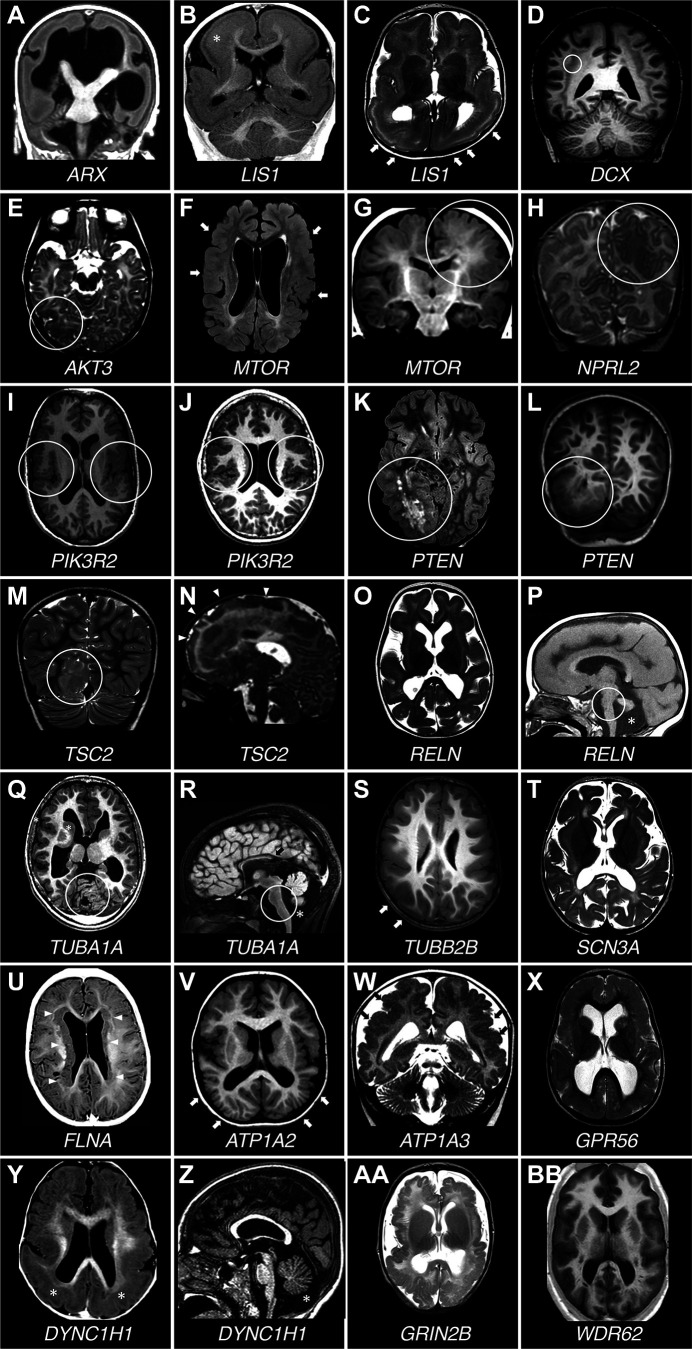

图 7.患有不同皮质发育畸形的患者的脑MRI。A : T1加权(T1W)冠状切面。一名患有ARX突变的男孩患有无脑畸形。脑室严重扩张,胼胝体缺失,基底神经节严重发育不全。B和C:患有后脑回>前脑回巨核细胞增生和皮质厚度增加的脑部的冠状T1W和轴位T2加权(T2W)切面。该男孩患有LIS1突变。B图中的白色星号表示皮质增厚较为严重的部位。C图中的白色箭头指向皮质更为光滑和厚实的区域。D : T1W冠状切面。一名患有DCX突变的女孩出现弥漫性皮质下带状异位。白色圆圈环绕着皮质下层状异位,该异位在皮质下方形成几乎连续的带状,由白质与其隔开。E :轴位T2W切面。一名女孩的右侧枕叶皮质发育不良(白色圆圈包围), AKT3基因存在极低水平镶嵌突变(脑内 0.67%,血液中未检测到)。F和G :2 名携带MTOR基因镶嵌突变且镶嵌率不同的患者的轴向液体衰减反转恢复 (FLAIR) 和冠状 T1W 切片(F:p.Thr1977Ile,血液中镶嵌率为 20%;G:p.Ser2215Phe,手术切除的发育不良脑组织中镶嵌率为 5.5%)。在F中,患者患有巨脑畸形,脑室较大,皮质多处异常区域交替出现内褶,表面光滑。这种模式提示多小脑回畸形(白色箭头)。G图中,白色圆圈突出显示皮质发育不良区域,脑实质体积增大,灰白质交界处模糊,皮质折叠不规则。H:T2W冠状切面。一名携带NPRL2突变的女孩的左侧顶颞叶局灶性皮质发育不良。圆圈围绕着皮质异常的顶叶部分。I和J:2名携带p.Gly373Arg PIK3R2基因突变且嵌合率不同的患者的T1W轴位切面( I :血液中嵌合率为13%,唾液中为43%;J :血液中嵌合率为10%,唾液中为29%)。两名患者均有双侧外侧裂周围多小脑回畸形(白色圆圈)。K和L:轴向 FLAIR 和冠状 T1W 切片显示患有体质性PTEN突变的男孩的右后象限发育不良(白色圆圈)。M和N:2 名患有体质性TSC2突变的患者的 T2W 冠状和矢状切片(M:p.Thr1623Ile;N:p.Pro1202His)显示由大型皮质结节(M,白色圆圈)引起的右后象限发育不良以及涉及大部分右额叶的广泛发育不良区域(N,白色箭头)。O和P :T2W 轴向和 T1W 矢状切片。患有RELN突变的女孩的平滑脑畸形,皮质厚度正常,小脑发育不全(P ,星号)。白色圆圈环绕着发育不全的脑干。Q和R :轴向和矢状 T1W 切片。一名携带TUBA1A突变的男孩,皮质增厚,脑回形态简化,小脑发育不全。圆圈环绕发育不全的小脑和脑干。星号表示发育不全的小脑蚓部下方区域,黑色箭头指向发育不全且缺乏最后部的胼胝体。S :T1W轴切面。一名携带TUBB2B突变的男孩,脑回形态弥漫性简化,侧裂明显增厚内翻。箭头指向皮质光滑区域。T :T2W轴切面。一名携带SCN3A突变的女孩,出现严重的脑回发育障碍,脑回形态简化。U :T1W轴切面。一名携带FLNA突变的女孩,出现典型的双侧脑室周围结节性异位。双侧室管膜下异位结节(白色箭头)连续,广泛覆盖于脑室壁。V :T1W 轴位切面。一名携带 ATP1A2 突变的男孩,脑内可见弥漫性多小脑回畸形,后部更为明显(白色箭头)。W : T2W冠状切面。一名携带ATP1A3突变的男孩,脑内可见多小脑回畸形,伴有异常皮质内褶和密集小脑回畸形(黑色箭头),并伴有异常脑沟。X :T2W 轴位切面。一名携带双等位基因GPR56突变的男孩,脑内可见双侧额顶叶皮质增厚和弥漫性异常皮质模式。Y和Z : T1W 轴位和矢状切面。一名携带DYNC1H1突变的女孩,脑回增厚和外侧裂周围多小脑回畸形。Y 轴位标有星号位于皮质增厚最严重的地方,即后皮质。Z 中的星号位于发育不全的小脑蚓部下方。AA : T2W 轴位。一名携带GRIN2B突变的男孩出现弥漫性多小脑回畸形。BB :T1W 轴位。皮质模式弥漫异常,皮质光滑,并有异常内褶区域,提示一名携带双等位基因 WDR62 突变的男孩患有多小脑回畸形。

MCD 的表型连续体包括局灶性皮质发育不良 II 型 (FCDII)、半巨脑畸形 (HME)、巨脑畸形 (MEG) 和发育不良性巨脑畸形 (DMEG),主要由 mTOR 通路基因的组成性和体细胞突变引起,即AKT1和AKT3(图 7 E)、DEPDC5和MTOR(图 7 F和 G)、NPRL2(图 7 H)、NPRL3、PIK3CA和PIK3R2(图 7 I和J)、PTEN(图 7 K和L)以及TSC1和TSC2(图 7 M和N),代表了由异常神经元增殖或分化以及异常神经元迁移引起的发育性癫痫性脑病 (DEE) 的范例。在因药物难治性癫痫而接受手术治疗的儿童中,近一半是由 FCD 引起的,粗略估计,在美国有近 40 万人(Wolters Kluwer UpToDate 网站,https://www.uptodate.com/contents/evaluation-and-management-of-drug-resistant-epilepsy)。除了皮质分层异常外,FCDII 还具有大的畸形神经元,这些神经元没有(IIa 型)球状细胞或有(IIb 型)球状细胞。HME 是一种一侧半球异常大于对侧半球的疾病,而 DMEG 是一种皮质发育不良与节段性脑过度生长有关的疾病,它们的组织病理学特征与 FCDII 相似。结节性硬化症 (TSC) 是一种先天性综合症,其特征是在包括大脑在内的多个器官中发展良性肿瘤 (错构瘤),并具有主要包括早发性癫痫、智力障碍和有时自闭症的神经系统表型,该综合症也是由肿瘤抑制基因TSC1或TSC2突变导致的 mTOR 通路失调引起的。